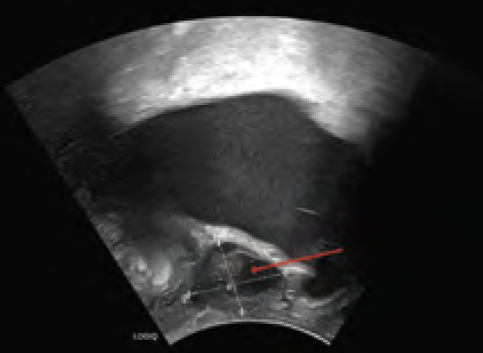

Introitussonographie: Suburethral gelegene zystisch, teils solide und durchblutete Raumforderung mit intakter Gewebslamelle zur Harnblase, circa 2,8 x 3,8 cm messend (siehe Abbildung 1).